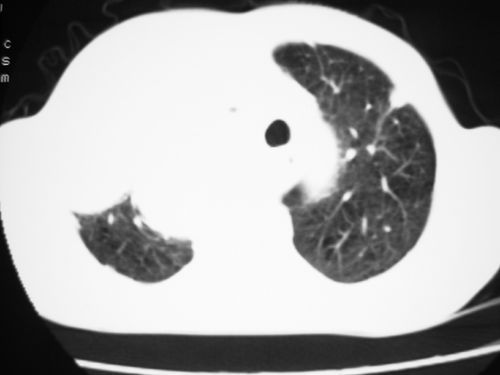

以下是引用yangyudong333在2008-4-29 5:46:00的发言:[br]1左上叶结节呈分叶状,边缘毛刺,考虑肺癌并纵隔淋巴结转移可能性大,结核待排,[br] [br]2右侧多发包裹性胸腔积液